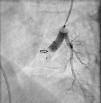

Varón de 13 años, con cuadro de tos de un mes de evolución sin respuesta a broncodilatadores ni antibioterapia. A la exploración física presentaba SO2 del 95% sin signos de dificultad respiratoria. La radiografía de tórax mostró una lesión nodular en la base pulmonar izquierda (fig. 1). Se realizó una ecocardiografía donde se halló una dilatación de la vena pulmonar inferior izquierda y la tomografía computarizada torácica con contraste confirmó la existencia de una malformación arteriovenosa pulmonar (MAVP) de gran tamaño a nivel del segmento anterobasal del lóbulo inferior izquierdo. Se llevó a cabo un cateterismo diagnóstico consistente en arteriografía pulmonar izquierda, observando dicha MAVP a nivel del lóbulo inferior izquierdo, con morfología aneurismática, de unos 20×15mm, irrigada por 2 arteriolas pulmonares y con cortocircuito derecha-izquierda de 1,6 lpm (fig. 2). Así mismo, se evidenciaron otras MAVP de pequeño tamaño, angiográficamente no significativas, en otros lóbulos segmentarios. Se realizó la embolización selectiva de la fístula mediante un dispositivo autoexpandible vascular Plugg II (AGA), sin incidencias durante el procedimiento y con resultado satisfactorio (fig. 3).